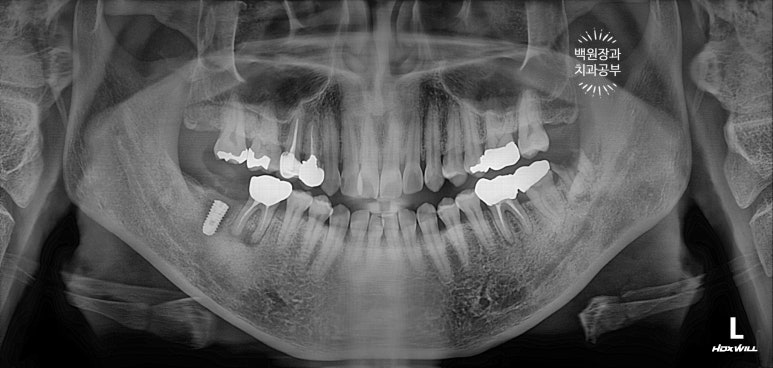

치과용 파노라마 엑스레이를 보니 오른쪽 아래 두번째 큰어금니와 왼쪽 아래 사랑니가 머리가 부러져 있네요.

그 중 오른쪽 아래 어금니는 신경치료를 하셨던 이빨인데, 이차 충치가 심해서 부러진 모양입니다.

그리하여 수술 후 치과용 파노라마 사진입니다.

임플란트 위치가 아주 듬직하니 마음에 드네요!!

임플란트 완성 후 치과용 파노라마 사진입니다.

임플란트가 이상적인 모양으로 예쁘게 제작된 것을 보실 수 있을거에요!